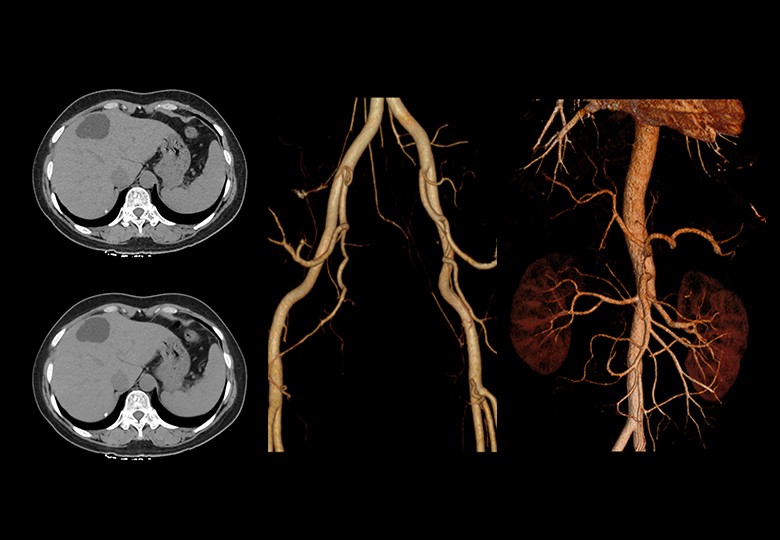

Album d'images cliniques

• Abdomen

• Vaisseau